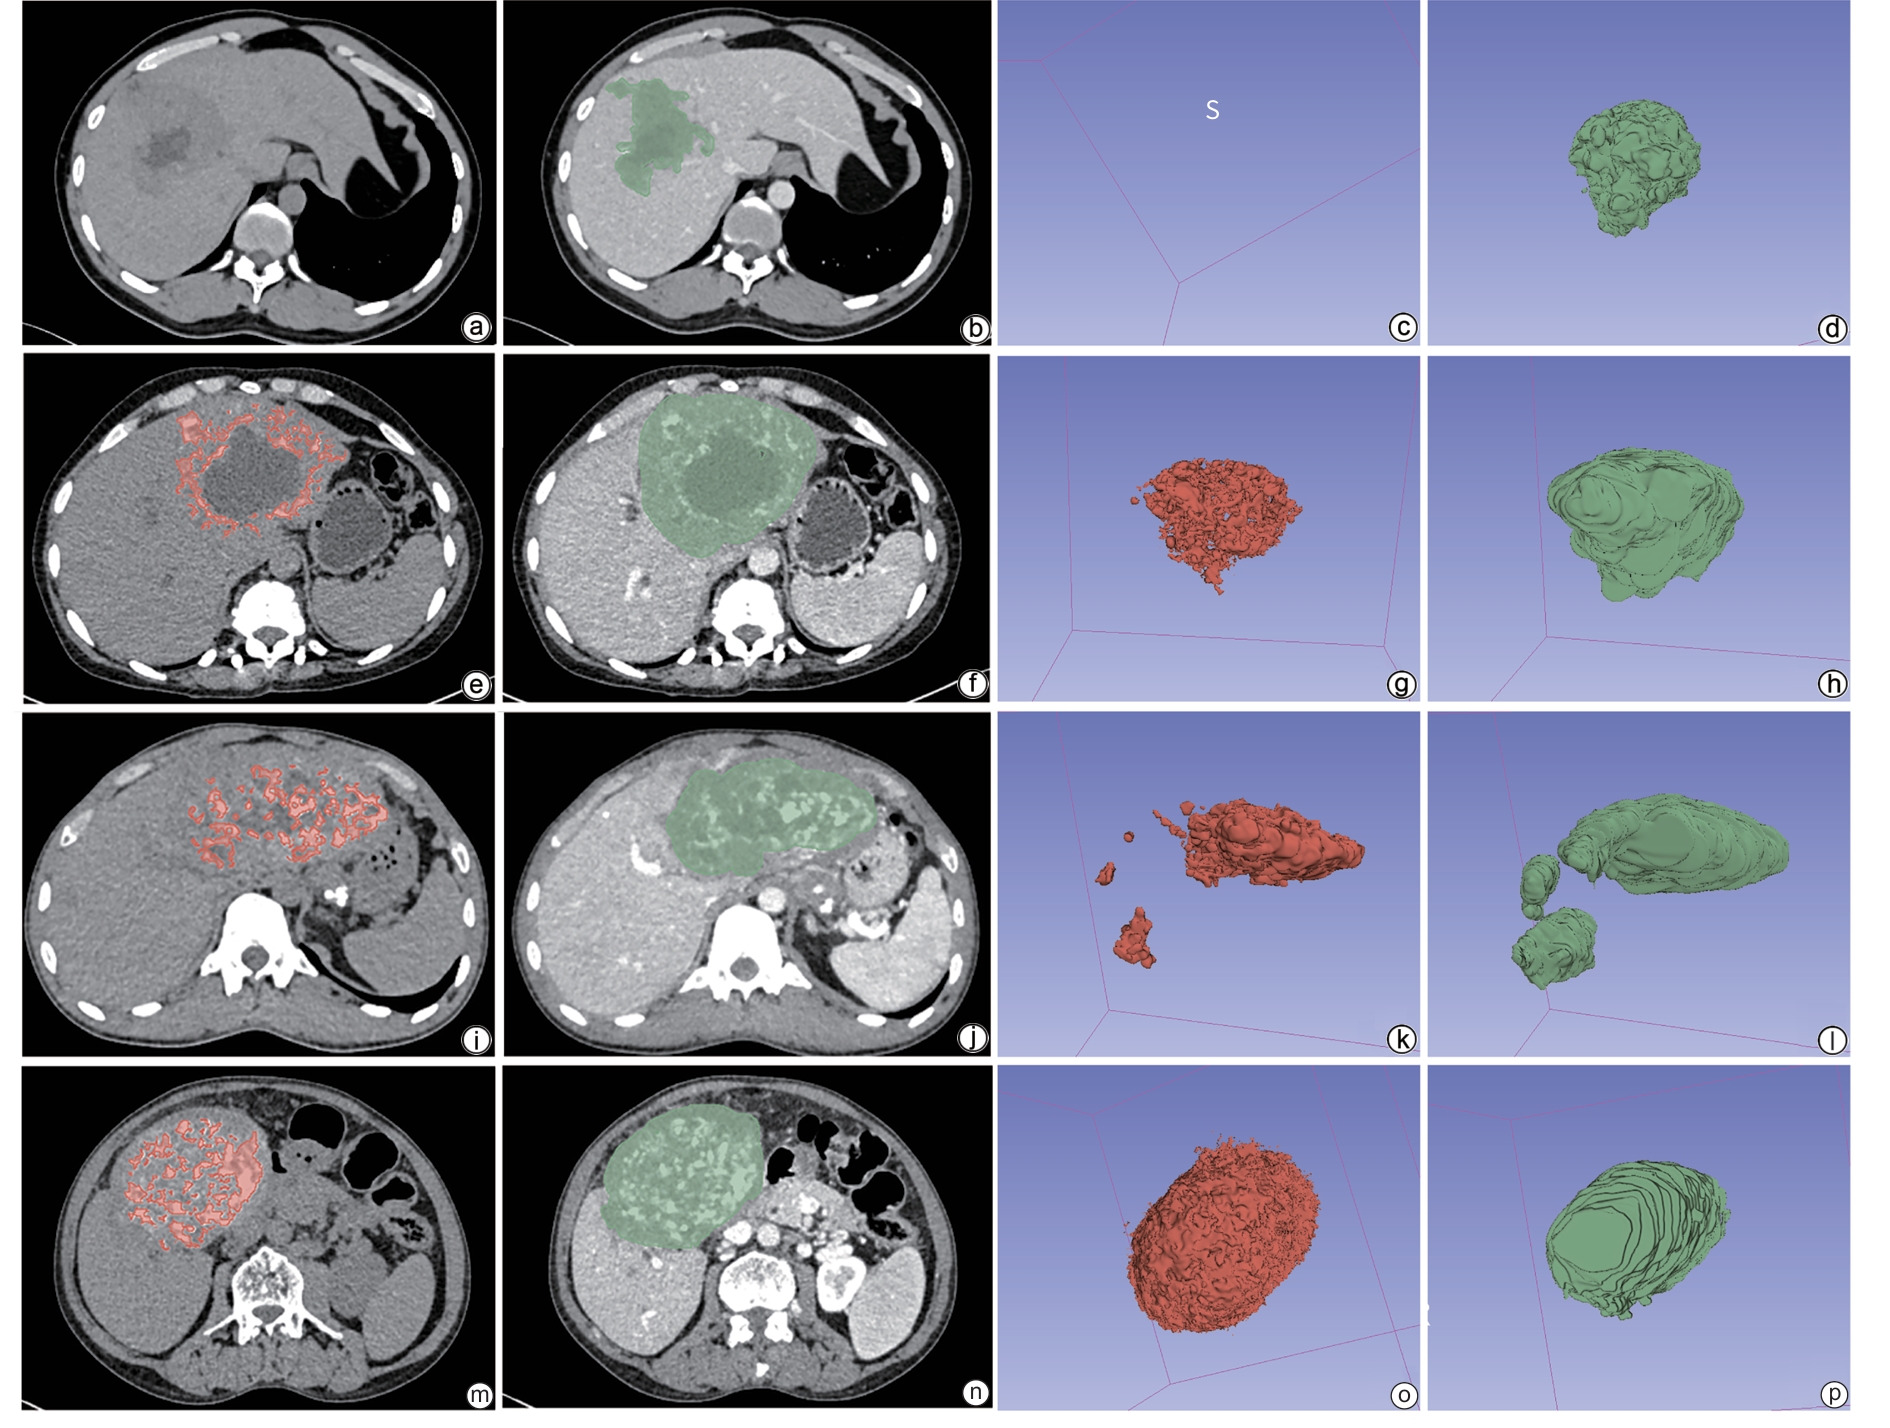

Influencing factors for calcium salt deposition in patients with alveolar echinococcosis

Zitong XIONG, Zhiyi LIN, Yanxin HUANG, Fuzhong FANG, Zhengzhan WU, Zirui XIN, Chunxia HU, Jiayu ZHOU, Yuan YAO, Hongwei ZHANG

2026, 42(2): 372-379. DOI: 10.12449/JCH260217

Abstract(141) HTML (73) PDF (14459KB)(66)

Abstract:

Objective  To investigate the imaging features of calcium salt deposition and serological markers in patients with alveolar echinococcosis through a retrospective analysis, as well as independent risk factors for the degree of calcium salt deposition in lesions, and to provide a basis for assessing disease process.  Methods  A retrospective analysis was performed for the imaging and clinical data of 107 patients with alveolar echinococcosis who were admitted to The First Affiliated Hospital of Shihezi University from December 2023 to June 2025, and according to the volume of calcium salt deposition, they were divided into non-deposition group with 16 patients, mild deposition group with 52 patients, moderate deposition group with 16 patients, and severe deposition group with 23 patients. A one-way analysis of variance or the Kruskal-Wallis H test was used for comparison of continuous data between groups, and the χ2 test or Fisher’s exact test was used for comparison of categorical data between groups. The four groups were further combined into the low deposition group (no/mild deposition) and the high deposition group (moderate/severe deposition). A binary logistic regression analysis was used to investigate the independent influencing factors for calcium salt deposition, and a predictive model was established. The receiver operating characteristic (ROC) curve was used to assess the predictive performance of the model, and the Bootstrap method was used for internal validation.  Results  There were significant differences between the four groups in sex distribution, involvement of other sites, white blood cell count, lymphocyte percentage, fibrinogen, uric acid, sodium ion, chloride ion, and calcium ion (all P<0.05). The univariate analysis showed that there were significant differences between the four groups in sex, involvement of other sites, white blood cell count, lymphocyte percentage, fibrinogen, alanine aminotransferase, albumin, creatinine, uric acid, sodium ion, chloride ion, and calcium ion (all P<0.1). The multi-collinearity diagnosis showed that the VIF values for all continuous variables ranged from 1.104 to 1.760, suggesting that collinearity did not affect modeling. An ordinal logistic regression model was established based on sex, involvement of other sites, calcium ion, lymphocyte percentage, and uric acid. The multivariate analysis showed that lymphocyte percentage (odds ratio [OR]=1.106, 95% confidence interval [CI]: 1.041 — 1.174, P=0.001) and blood calcium level (OR=0.005, 95%CI: 0.000 —0.230, P=0.007) were independent influencing factors for the degree of calcium salt deposition. The regression equation was established as Logit(P)=8.231 + 0.100 × lymphocyte percentage -5.344 × calcium ion. The ROC curve analysis showed that the model had an area under the ROC curve of 0.716, with a Youden index of 0.353, a sensitivity of 1.000, and a specificity of 0.353. The Hosmer-Lemeshow test showed that the model had poor calibration (χ2=20.688, P=0.008). The Bootstrap method with 1000 repeated samples showed that the estimated values of lymphocyte percentage (OR=1.106, 95%CI: 1.049 — 1.186, P=0.002) and calcium ion (OR=0.005, 95%CI: 0.000 — 0.214, P=0.010) were consistent with the original model, and the confidence intervals did not include 1, which further supported the reliability of the model.  Conclusion  Both lymphocyte percentage and blood calcium level are independent influencing factors for calcium salt deposition in alveolar echinococcosis, and the degree of calcium salt deposition in alveolar echinococcosis lesions increases with the reduction in blood calcium level and the increase in lymphocyte percentage.